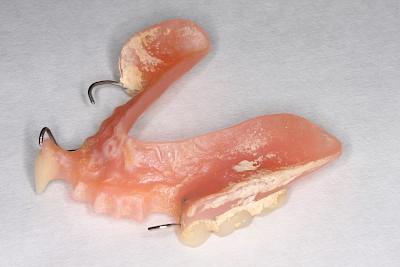

Hält eine Teilprothese kann es auch sein, dass das Verbindungselement defekt oder verlorengegangen ist. In diesen Fällen ist zu prüfen, ob eine Klammer abgebrochen oder ein Verbindungselement wie z. B. eine Krone fehlt. Ist dies der Fall muss ein Zahnarzt gerufen werden.

Bei manchen Prothesen verschlechtert sich der Halt, weil die Haltewirkung der Verbindung zwischen der Prothese und den Restzähnen oder Implantaten nachlässt. Nicht selten sind auch einzelne Verbindungs- bzw. Verankerungselemente einfach "verloren" gegangen (verschluckt, ausgespuckt und ganz selten aspiriert!). Manchmal stecken die Kronen, die die Prothese mit den Restzähnen verbinden, in der herausnehmbaren Prothese. In Ausnahmefällen sind die Ankerzähne oder Implantate selbst nicht mehr im Knochen fest verankert und gehen mit der Prothese insgesamt raus. In allen diesen Fällen sollte der Zahnarzt gerufen werden.